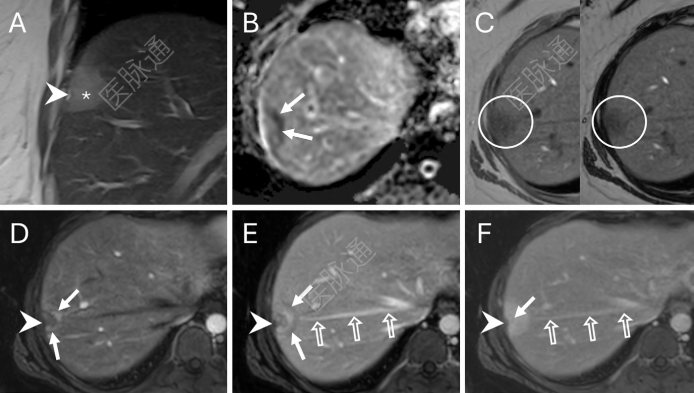

图2:腹部MRI扫描,重点显示第7段病灶。(A) 冠状面T2加权单激发快速自旋回声图像显示包膜下肿块呈T2中等信号(*),伴有包膜皱缩(箭头)。(B) 轴位表观弥散系数(ADC)图显示边缘弥散受限(箭头)。(C) T1加权同相位(左)和反相位(右)图像显示反相位信号无减低,提示无微观脂肪(圆圈)。(D–F) 增强扫描显示动脉晚期环形强化(D中箭头)、门脉期边缘洗脱(E中实线箭头)和延迟期中心强化(F中实线箭头)。此外,一条右肝静脉大分支(E、F中的空心箭头)从病灶内侧缘发出(即棒棒糖征)。箭头指示包膜皱缩。(D)动脉晚期、(E)门静脉期及(F)平衡期示动脉期环形强化(D 图箭头)、外周廓清(E 图实心箭头)及延迟期中心强化(F 图实心箭头)。此外,可见一粗大肝右静脉属支(E、F空心箭)自病灶内侧缘发出(即棒棒糖征),箭头尖指示包膜皱缩。